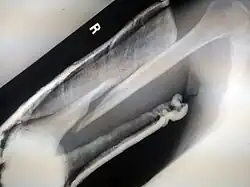

A bone fracture (abbreviated FRX or Fx, Fx, or #) is a medical condition in which there is a partial or complete break in the continuity of any bone in the body. In more severe cases, the bone may be broken into several fragments, known as a comminuted fracture.[1] An open fracture (or compound fracture) is a bone fracture where the broken bone breaks through the skin.[2]

- Open/compound fractures involve wounds that communicate with the fracture, or where fracture hematoma is exposed, and may thus expose bone to contamination. Open injuries carry a higher risk of infection. Reports indicate an incidence of infection after internal fixation of closed fractures of 1-2%, rising to 30% in open fractures.[12]